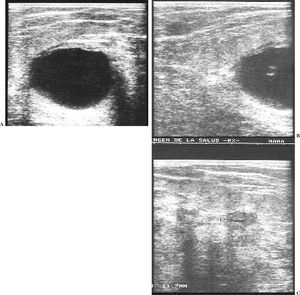

El fibroadenoma fue la tumoración más frecuente en nuestro estudio y ecográficamente se presentó como nódulos ecogénicos homogéneos con márgenes definidos, alguno de ellos lobulado, y que a diferencia de los fibroadenomas en mujeres no embarazadas presenta una gran proliferación glandular o adenomatosa del nódulo, con abundante estroma fibroso y cambios secretores (fig. 3).

Fig. 3.--Fibroadenoma. Ecografía mamaria. (A) Nódulo ecogénico y homogéneo con margen definido. (B) Hematoxilina x20-x40. Célula típica con abundante estroma con cambios secretores.

El aspecto ecográfico más frecuentemente descrito en la literatura es el de un nódulo hipoecoico con respecto al tejido glandular circundante y homogéneo con refuerzo acústico posterior con o sin lobulación18. No obstante, nosotros tuvimos tres casos de nódulos isoecoicos, heterogéneos e incluso uno de ellos con áreas con sombra acústica posterior (fig. 4), probablemente porque un 5% de los adenomas de la lactancia exhiben zonas de infarto, lo que puede tener traducción en la imagen.

Fig. 4.--Adenoma de lactancia. Ecografía mamaria. (A) Nódulo ligeramente hipoecoico y homogéneo con refuerzo posterior. (B) Hematoxilina x40 células monomorfas dispuestas en lobulillos. (C) Nódulo isoecoico, heterogéneo con septos y áreas con sombra acústica posterior. (D) Cilindro de BAG. Hematoxilina x20. Cambios secretores con células monoformas en lobulillos.

Ecográficamente son lesiones solitarias hipoecoicas con pared fina y refuerzo posterior20,21 (fig. 5).

Fig. 5.--Galactocele. Ecografía mamaria. (A) Nódulo hipoecoico y homogéneo. Drenaje del mismo. (B) Nódulo heterogéneo de ecogenicidad mixta por su contenido proteináceo.